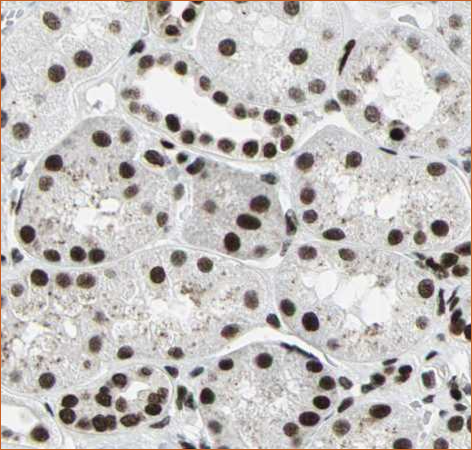

CytoSection control slides maintain the cellular localization patterns of nuclear and cytoplasmic/membrane-associated proteins, closely mirroring their distribution in tissue samples.

Nuclear localization of BRG1

BRG1 antibody of kidney tissue. Image source: Protein atlas

DDK-tag detection of BRG1 in CytoSection ()